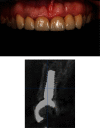

Anterior aesthetic zone implant placement and tooth restoration can be a quite challenging procedure. Modern technology offers new tools that can help maximize results in both aesthetic and functional ways. The socket-shield technique, as described by Hürzeler et al., boosted with the 3D diagnostics, digital planning, and 3D printing, could provide a valuable alternative to traditional approaches. This case report describes a clinical workflow for an efficient anterior implant-prosthetic restoration.